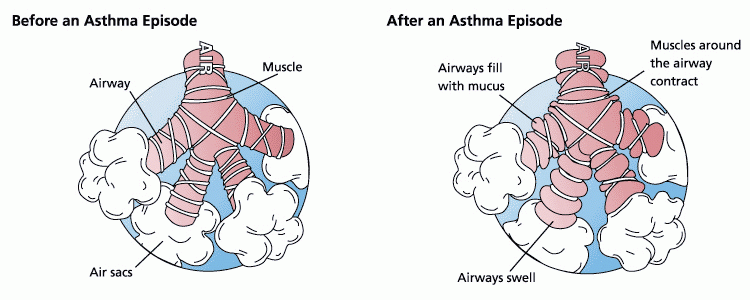

- Asthma

- Asthma is a respiratory disease of the bronchi and bronchioles. The symptoms include wheezing, shortness of breath, and sometimes a cough that will expel mucus. The airways are very sensitive to irritants which can include pollen, dust, animal dander, and tobacco. Even being out in cold air can be an irritant. When exposed to an irritant, the smooth muscle in the bronchioles undergoes spasms. Most asthma patients have at least some degree of bronchial inflammation that reduces the diameter of the airways and contributes to the seriousness of the attack.